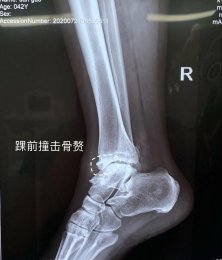

專于骨科,精于微創(chuàng)。濰坊市市立醫(yī)院骨二科以骨科微創(chuàng)為主要特色,致力于用最小的創(chuàng)傷治療疾患,并結(jié)合ERAS理念,創(chuàng)建無痛手術(shù)、無痛病房,給予患者最快最佳的術(shù)后恢復(fù)??剖议_展髖膝關(guān)節(jié)疾病的個(gè)體化治療,充 分評(píng)估患者髖膝關(guān)節(jié)功能,從采用不同的 手術(shù)方案治療髖膝關(guān)節(jié)疼痛; 開展 微創(chuàng)經(jīng)皮椎弓根螺釘內(nèi)固定術(shù)、經(jīng)皮椎體成形術(shù)(PVP、PKP)術(shù)、MIPPO技術(shù)等各種骨科...[全文閱讀]